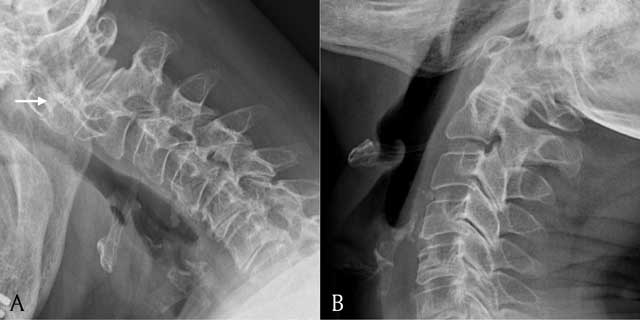

Figure 3

A = lateral view of the cervical spine in flexion; B = lateral view of the cervical spine in extension. Plain radiograph showing a lateral view of the cervical spine in flexion and extension. Note widening of the atlantodental interval in flexion (white arrow).